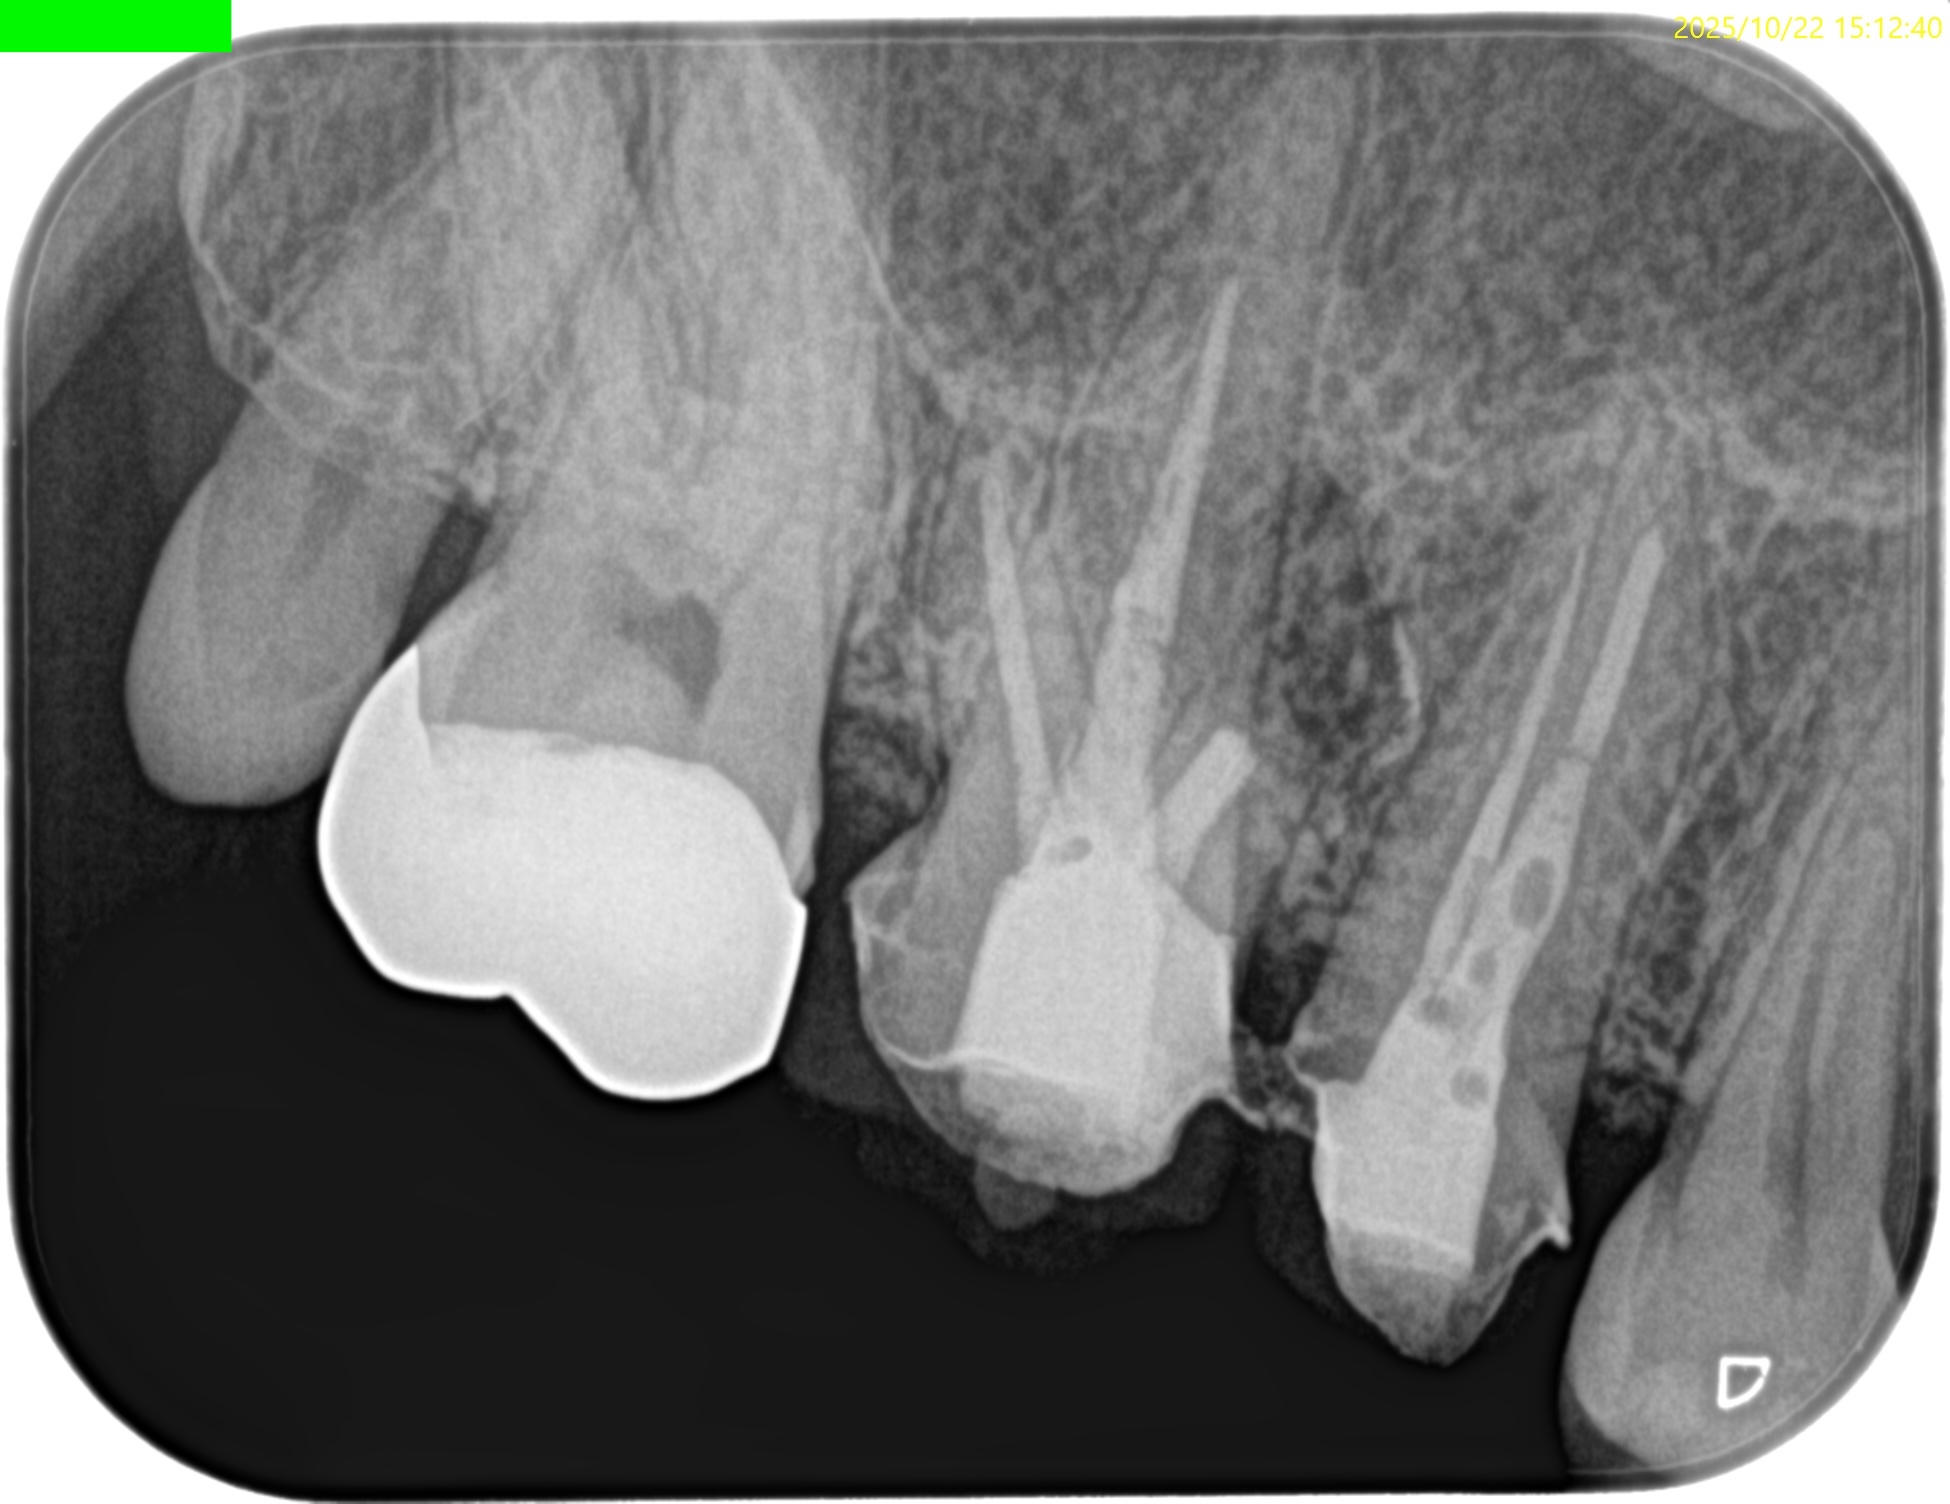

#3 MB Apicoectomy(2025.10.22)

CEJよりも10mm下方の#3 MBのApexをOsteotomyで探索する。

このApexから4mmの部分を想定しRoot resectionした。

今回は折れたFileごとMBのApexを除去した形だ。

この後メチレンブルーで染めて逆根管形成した。

逆根管充填した。

術後にPA, CBCTを撮影した。

問題はないだろう。